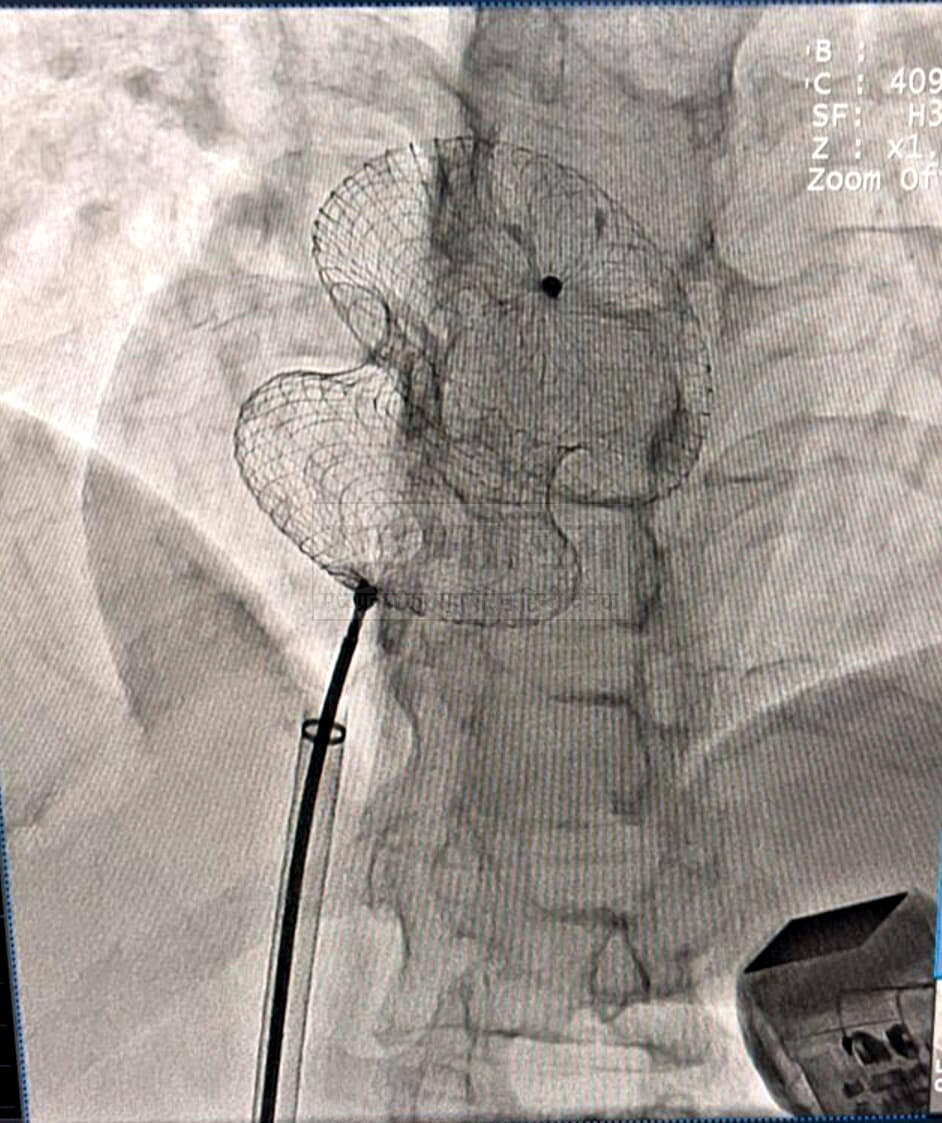

रीवा। सुपर स्पेशलिटी हॉस्पिटल रीवा के कार्डियोलॉजी विभाग ने एक नया कीर्तिमान स्थापित किया है। डॉ. एसके त्रिपाठी एवं डॉ. सुरेंद्र तिवारी की अगुवाई में टीम ने दो मरीजों के दिल में बड़े जन्मजात छेद (एट्रियल सेप्टल डिफेक्ट -एएसडी) को बिना ओपन हार्ट सर्जरी के, मात्र एक छोटी सी डिवाइस के माध्यम से सफलतापूर्वक बंद कर दिया।

यह आधुनिक प्रक्रिया पहले केवल बड़े चीरे और ओपन हार्ट सर्जरी से ही संभव थी, लेकिन अब कैथेटराइजेशन तकनीक से बिना किसी टांके या बड़े ऑपरेशन के यह इलाज हो रहा है। सबसे महत्वपूर्ण बात यह है कि विंध्य क्षेत्र में पहली बार एक ही समय में दो एएसडी डिवाइस क्लोजर प्रक्रियाएं सफलतापूर्वक संपन्न हुई हैं - यह क्षेत्रीय चिकित्सा इतिहास में एक मील का पत्थर है।